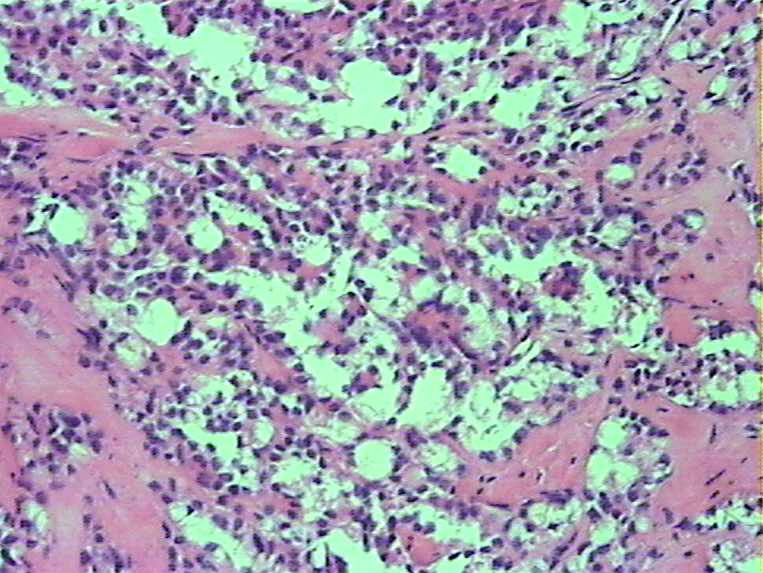

胰腺肿物 大体:灰白色肿物一枚大小:3*2*2cm,切面实性,质中。女,52

• 胰腺肿瘤图1

图1

胰腺实性-假乳头状瘤

实性假乳头状瘤

胰腺实性-假乳头状肿瘤(低级别恶性肿瘤)

会诊实性假乳头状瘤

胰腺实性-假乳头状肿瘤

胰腺实性假乳头状瘤